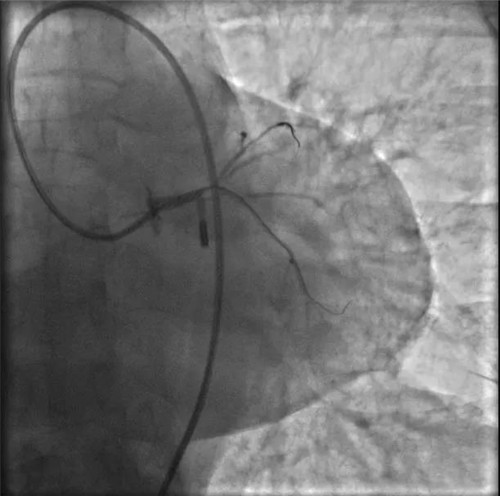

IABP(主動(dòng)脈內(nèi)球囊反搏)

突發(fā)的狀況并沒(méi)有打亂團(tuán)隊(duì)的陣腳,待生命體征穩(wěn)定后,決定先植入IABP(主動(dòng)脈內(nèi)球囊反搏)提供循環(huán)支持,防止病情進(jìn)一步惡化。穿刺雙側(cè)股動(dòng)脈,分別置入IABP導(dǎo)管及左冠指引導(dǎo)管。

因患者股動(dòng)脈扭曲,導(dǎo)管操控困難,術(shù)者反復(fù)嘗試,以導(dǎo)絲飄進(jìn)左主干,在球囊的支撐下,通過(guò)閉塞段到達(dá)中間支,小壓力擴(kuò)張后造影可見(jiàn)主干末端嚴(yán)重狹窄。隨后小心操控導(dǎo)絲到達(dá)回旋支、前降支,送入球囊擴(kuò)張,嚴(yán)重狹窄的左主干末端被撐開(kāi),左冠血流終于恢復(fù),胡女士暫時(shí)轉(zhuǎn)危為安。

球囊擴(kuò)張后,左冠血流恢復(fù),但左主干末端重度狹窄

左主干末端呈三分叉,前降支、回旋支均存在彌漫性病變,且血管非常細(xì)小,這是一個(gè)相當(dāng)復(fù)雜的左主干分叉病變。冒然植入支架,可能導(dǎo)致支架邊緣夾層、分支閉塞、慢血流等并發(fā)癥,稍有不慎,都會(huì)給患者帶來(lái)災(zāi)難性的后果。心血管內(nèi)科團(tuán)隊(duì)慎重決定,暫不植入支架,在IABP支持下,待血流沖刷冠狀動(dòng)脈,血管痙攣解除、血管擴(kuò)張后,再在IVUS(血管內(nèi)超聲)指導(dǎo)下植入支架。